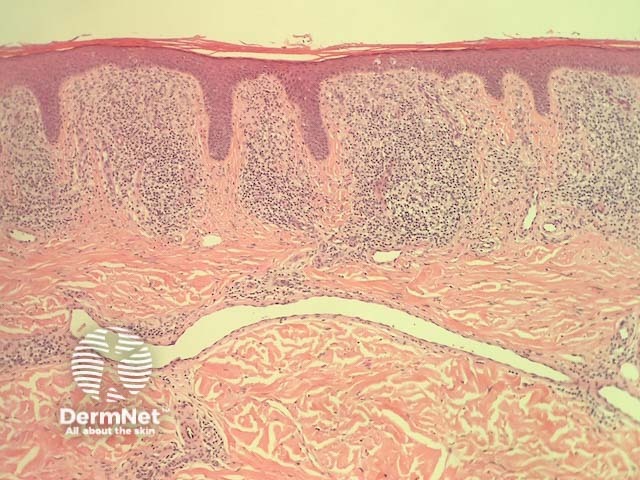

In lichen aureus, sections typically show a distinct pattern of infiltration in all types of pigmented purpuric dermatitis, with infiltration around the small vessels of the superficial plexus and minimal epidermal reaction (figure 1). At higher power, the infiltrate is mainly composed of lymphocytes with quite an impressive proportion of histiocytes (figure 2). The vessels may have some prominence of the endothelial cells but there is no evidence of vascular damage. A key feature of all types of pigmented purpuric dermatitis is the presence of haemosiderin within the superficial dermis, which results from chronic leakage of red blood cells from the vessels.

Figure 1